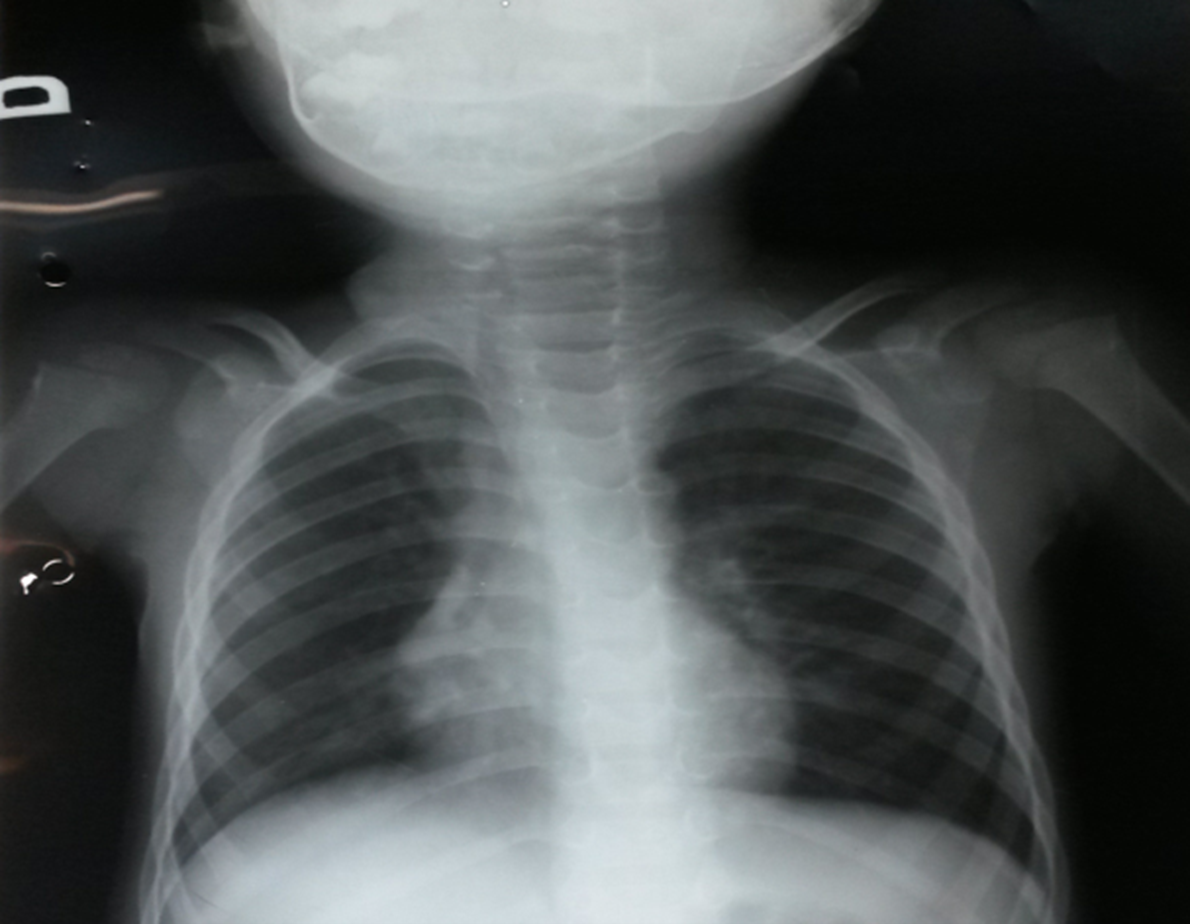

When Pulmonary Tuberculosis Leads to Pneumothorax: An Unusual Presentation

Catarina Bettencourt Giesta, Manuel d'Almeida, Sara Pires Ferreira